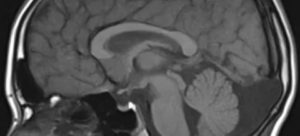

Несмотря на то, что КТ позволяет точно определить размеры и расположение кисты, наиболее точную и полную информацию об образовании дает МРТ. Обычно для диагностики арахноидальной кисты проводится МРТ-сканирование с введением в кровоток пациента контраста.

Картина арахноидальных изменений ликворокистозного характера в ходе исследований МР и КТ показывает наличие очагов с плотностью цереброспинальной жидкости, что подтверждает кистозную, неопухолевую природу образования.

Арахноидальная киста головного мозга, которая является наиболее распространенным типом кист среди мозговых образований и встречается у 4% людей, представляет собой мешочек, заполненный ликвором (цереброспинальной или спинномозговой жидкостью). Этот мешочек располагается в арахноидальной оболочке мозга. В области кисты ткань арахноидальной оболочки разделяется на два слоя, между которыми скапливается жидкость.